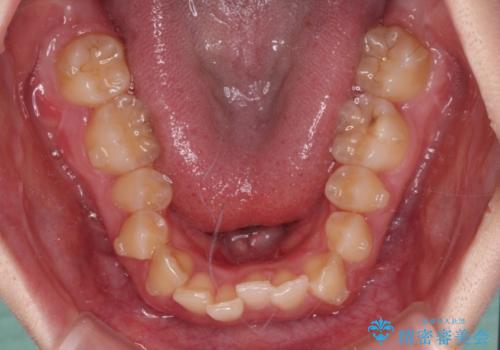

- 全体的な歯列の叢生を気にして来院された患者様です。

奥歯の咬み合わせを見ると、片方は上顎が下顎に対して相対的に前方にあり、他方は交叉した咬合の状態でした。

咬み合わせを改善するためには、上顎臼歯を後方に移動させた咬み合わせにする必要があります。

インビザライン単体で改善することも可能ですが、ディープバイトのためインビザライン単体で達成する可能性が低いと考えられたため、カリエール・ディスタライザーという補助装置を併用して、より確実性を上げることとしました。

カリエール・ディスタライザーを使用している期間、反対側はワイヤー矯正により叢生を解消していくこととしました。

奥歯の咬み合わせを改善しながら、並行してインビザラインで歯列を整えることとしました。